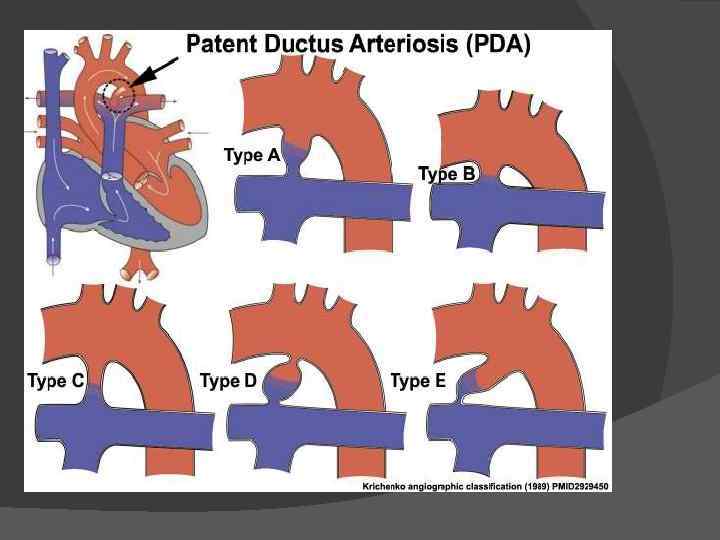

Этиология В некоторых случаях, причина которых неясна, проток не закрывается и остается сообщение между аортой и легочной артерией. Частота этого порока довольно велика и составляет 10 -25% всех врожденных сердечных аномалий. У женщин порок встречается чаще (7080% случаев)